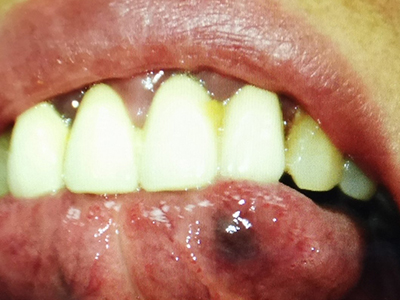

静脉湖下嘴唇有个紫色的疙瘩图

静脉湖表现为下嘴唇出现单个皮损,多为粟粒大小或米粒大小的疙瘩,颜色为暗紫色,边界清楚,高出皮面,不具有疼痛等不适感觉,多见于长期户外生活的人。